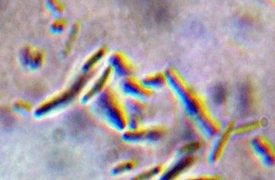

子牛ジフテリアは、世界中の若齢子牛(5週齢~24ヶ月齢)に発生する壊死性喉頭炎であり、フソバクテリウム・ネクロフォーラム(Fusobacterium necrophorum)細菌による喉頭組織の感染によって引き起こされます。この疾患は急性ま...